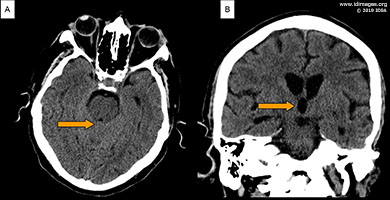

Computed tomography (CT) of the head (Figure 1A and B) and chest demonstrated obstructive hydrocephalus with tectum and midbrain edema and a 1.1 cm, noncalcified pulmonary nodule in the left lower lobe posteriorly (Figure 2).

- Figure 2: Computed Tomography of the chest without contrast demonstrating a 1.1 cm solid noncalcified nodule in the left lower lobe posteriorly.